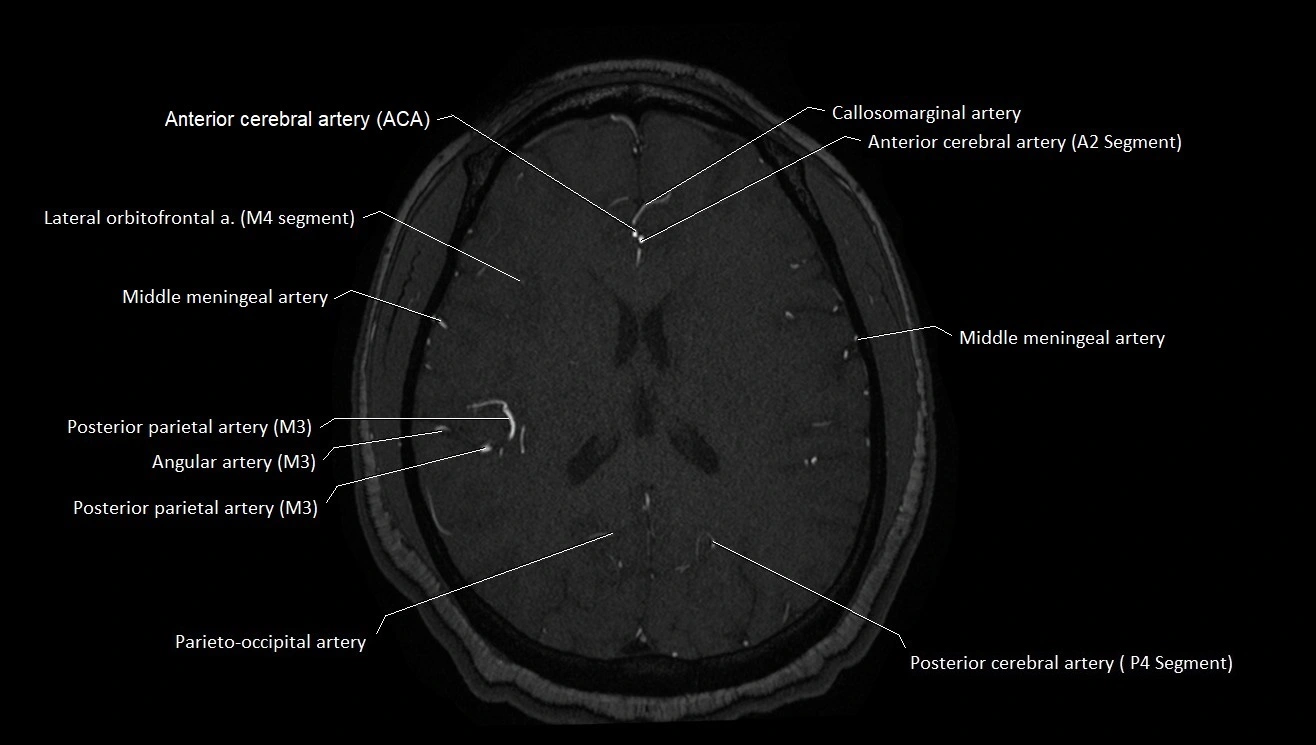

MRI images

image

CT images